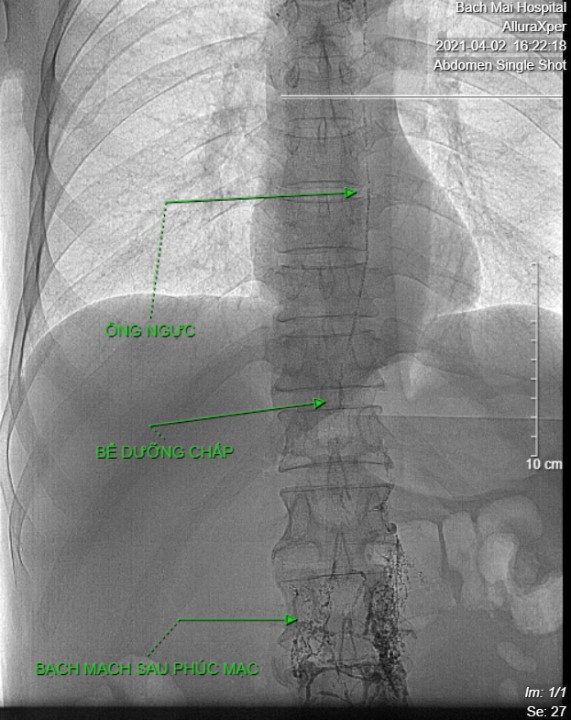

| Ảnh 1: Lipiodol được tiêm vào hạch bẹn hai bên, vào bạch mạch tiểu khung và di chuyển dần lên trên. | Ảnh 2: Lipiodol đi vào bạch mạch sau phúc mạc, sau đó đi vào bể dưỡng chấp, vào ống ngực, rồi đổ vào tĩnh mạch dưới đòn trái |

Ảnh 3. Chụp bạch mạch DSA cho thấy ống ngực có hình thái bình thường, đổ vào tĩnh mạch dưới đòn trái. Lipiodol tràn vào bạch mạch trung thất.

Ảnh 4. Chụp CT sau chụp DSA cùng bệnh nhân, thấy bạch mạch sau phúc mạc, bể dưỡng chấp và ống ngực. Lipiodol trong bạch mạch trung thất